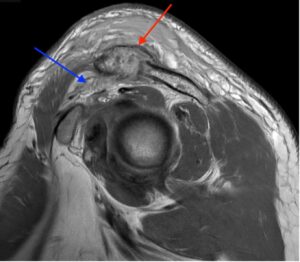

Septic Arthritis of AC Joint. MRI Sagittal. Annotated. JETem 2024